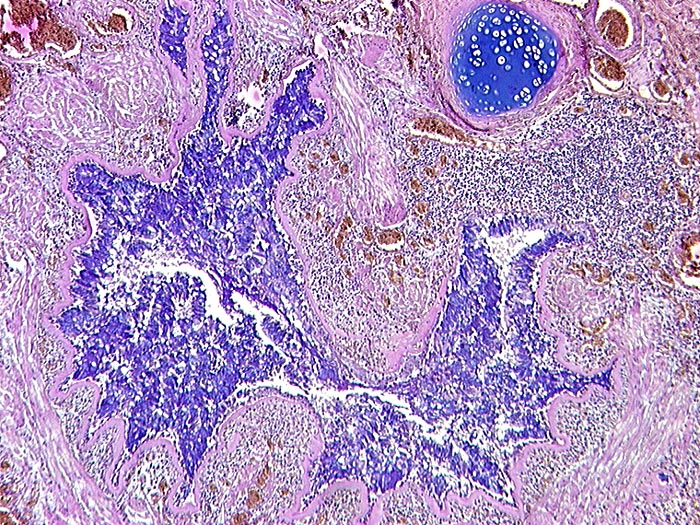

AP/ Asthma bronchiale

Asthma bronchiale

Bronchus

Pathologischer Befund